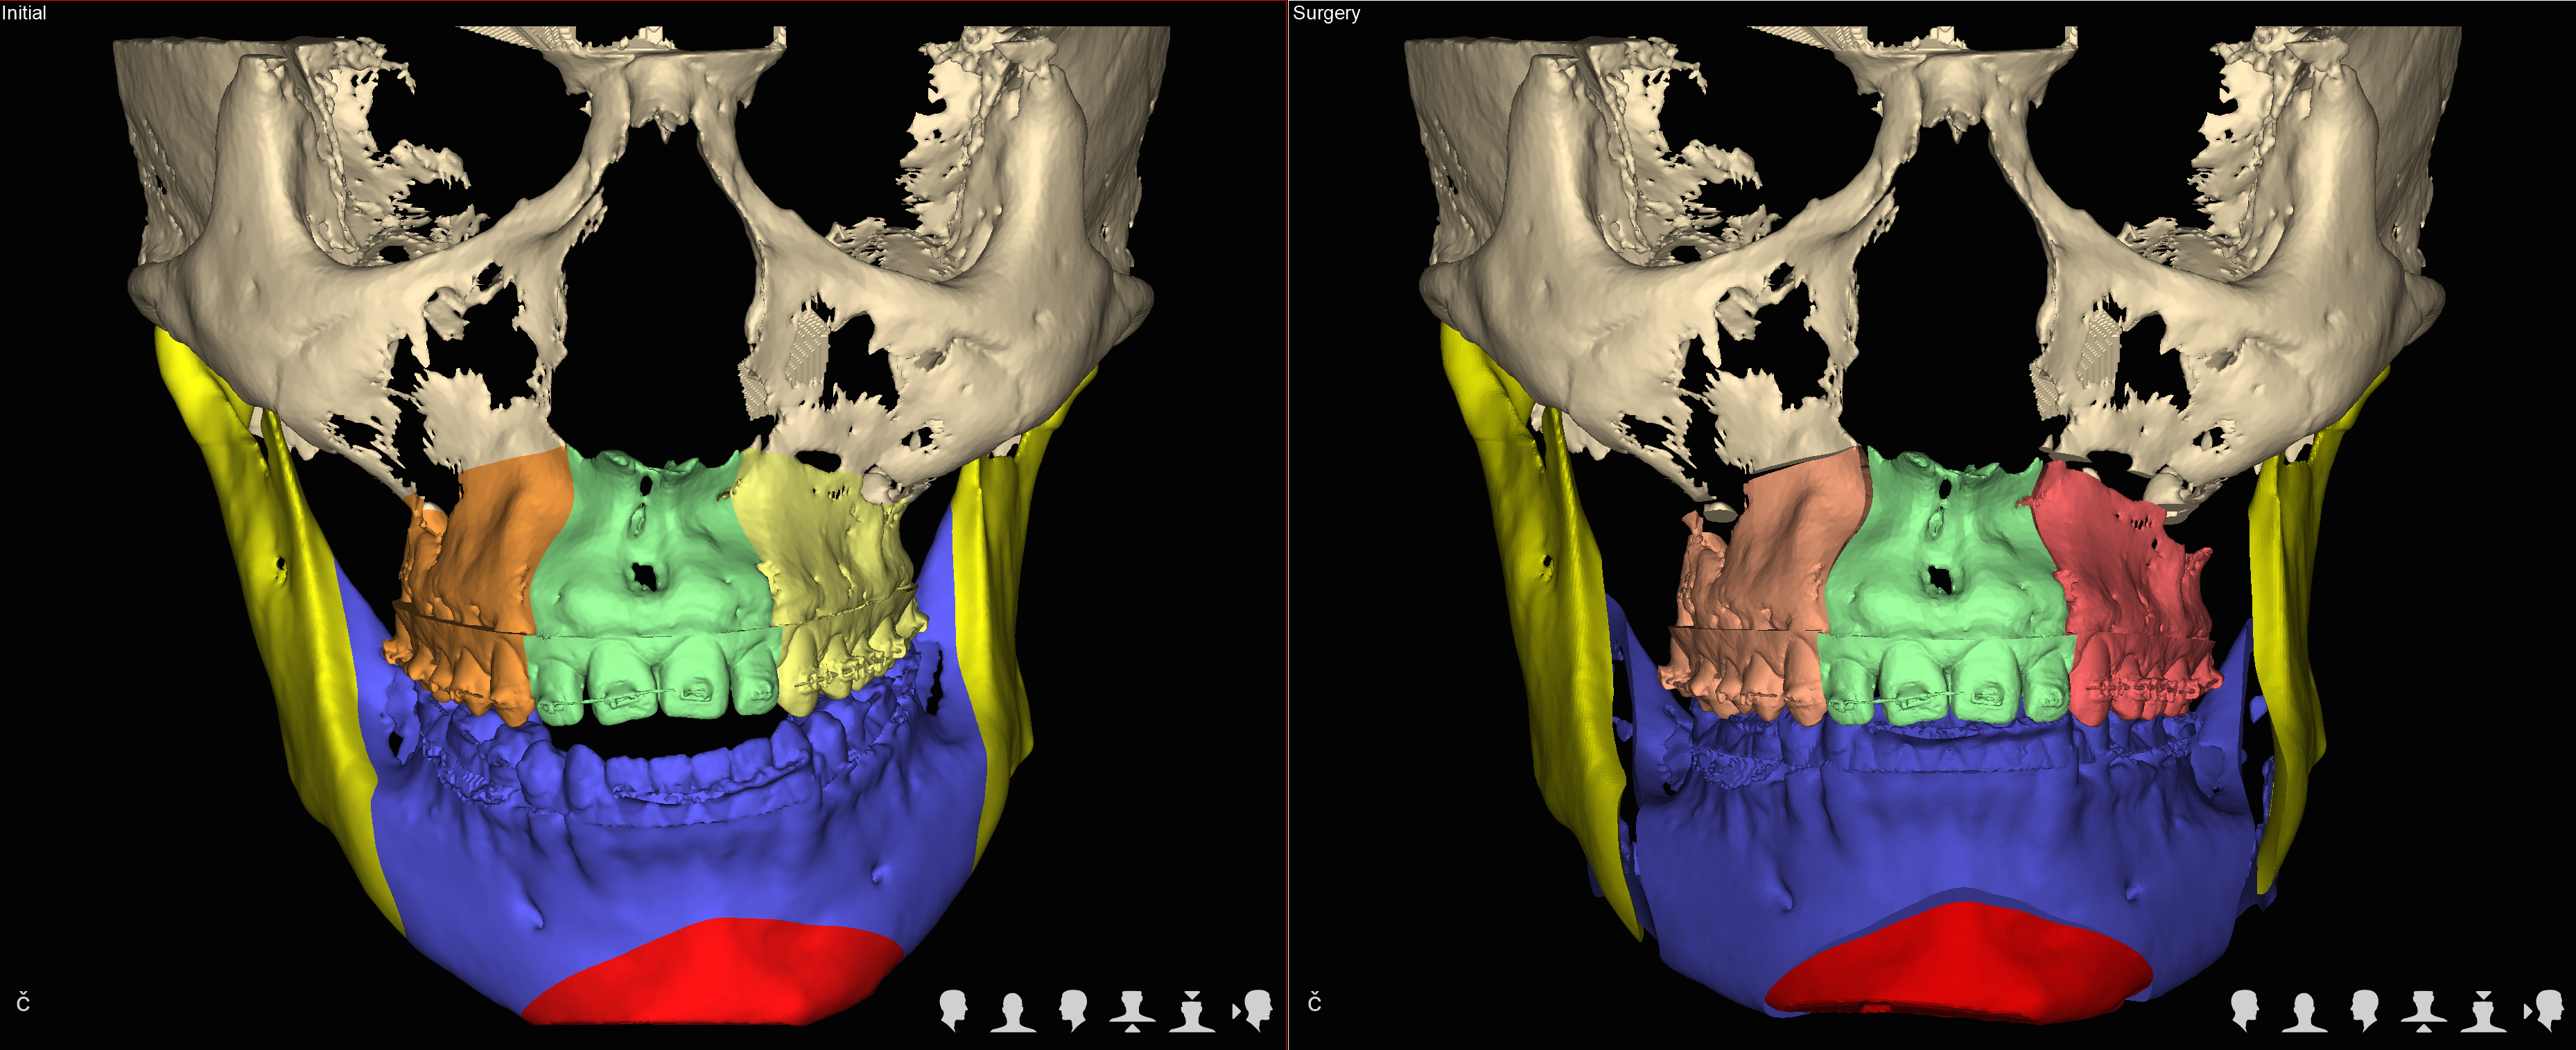

Trójwymiarowe planowanie leczenia wad zgryzu

Nie wyobrażamy sobie planowania operacji wady zgyzu inaczej niż w środowisku 3D.

We współczesnej chirurgii ortognatycznej uzyskanie prawidłowych warunków okluzyjnych czyli prawidłowego zgryzu jest jednym z celów leczenia równie istotnych jak zachowanie prawidłowych stosunków objętościowych w drogach oddechowych czy uzyskanie optymalnej estetyki twarzy.

Jedną z najistotniejszych części leczenia interdyscyplinarnego pacjentów z wadami szkieletowymi jest właściwe zaplanowanie całego procesu leczenia zarówno pod względem przesunięć zębów jak też zmian w układzie kostnym.

Szkielet czaszki twarzowej jest bryłą przestrzenną i rozpatrywanie jego nieprawidłowości w układzie trójwymiarowym pozwala na prawidłowe ich zdiagnozowanie a tym samym na optymalne zaplanowanie przesunięć kostnych, uzyskanie właściwych proporcji twarzy.

W naszym Centrum wykorzystujemy koncepceję FAB (FaceAirwayBite) opracowaną przez Williama Arnetta – światowej sławy chirurga zajmującego się leczeniem wad zgryzu.

U każdego Pacjenta rozpoczynającego leczenie w naszym Centrum po wykonaniu badań diagnostycznych przeprowadzamy szczegółowe analizy dotyczące wzajemnych relacji kostnych w obrębie twarzy, ustawienia zębów, projekcji tkanek miękkich i estetyki twarzy.

Następnie rekomendujemy lub wdrażamy postępowanie ortodontyczne. Po jego zakończeniu przystępujemy ponownie do analiz wszystkich parametrów w obrębie twarzy i przygotowujemy plan leczenia chirurgicznego obejmjący przesunięcia kostne z zakresie układu szkieletowego z uwględnieniem koncepcji FAB.

Docelowo efektem jest wydruk szablonów chirurgicznych na drukarce 3D.

W trakcie planowania powstają rownież symulacje efektów leczenia (symulacje a więc nie gwarantowany efekt), które są przedstawiane pacjentowi przed wykonaniem zabiegu.